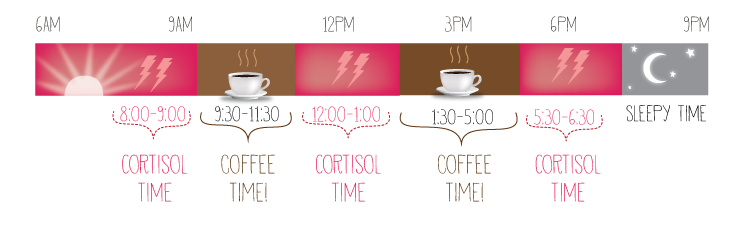

3. Waktu terbaik untuk minum kopi

Itu karena kita semua dipandu oleh siklus biologis 24 jam, yang dikenal sebagai jam sirkadian. Ketika Anda pertama kali bangun otak Anda sudah dibanjiri dengan kortisol, zat kimia alami yang membantu untuk membuat Anda waspada. Jadi meskipun Anda mungkin merasa butuh kopi, Anda sebenarnya belum membutuhkan itu. Sebaiknya tunggu sampai tingkat kortisol turun terlebih dahulu.

Itu karena kita semua dipandu oleh siklus biologis 24 jam, yang dikenal sebagai jam sirkadian. Ketika Anda pertama kali bangun otak Anda sudah dibanjiri dengan kortisol, zat kimia alami yang membantu untuk membuat Anda waspada. Jadi meskipun Anda mungkin merasa butuh kopi, Anda sebenarnya belum membutuhkan itu. Sebaiknya tunggu sampai tingkat kortisol turun terlebih dahulu.